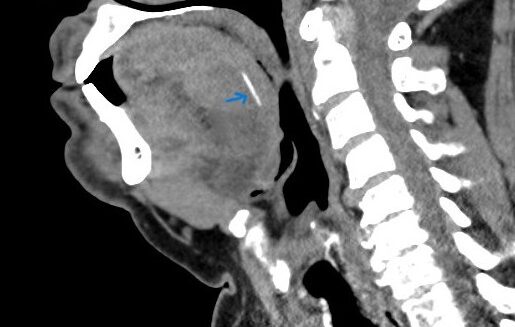

תושב סח’נין בן 65, אשר חש כאבים עזים בפיו לאחר אכילת דג, פונה למרכז הרפואי זיו בעקבות זיהום ונפיחות בלשונו. בעקבות ערנותו של ד”ר ג’מאל גנטוס, מתמחה א.א.ג, בוצעה בדיקת CT שאבחנה עצם דג באורך 2 ס”מ הנעוצה בעומק הלשון של המטופל ועלולה הייתה לסכן את דרכי הנשימה. בניתוח יוצא דופן, תחת הדמיית אולטרסאונד בזמן אמת, הצליח צוות מומחי המרכז הרפואי זיו, לשלוף את העצם בהצלחה.